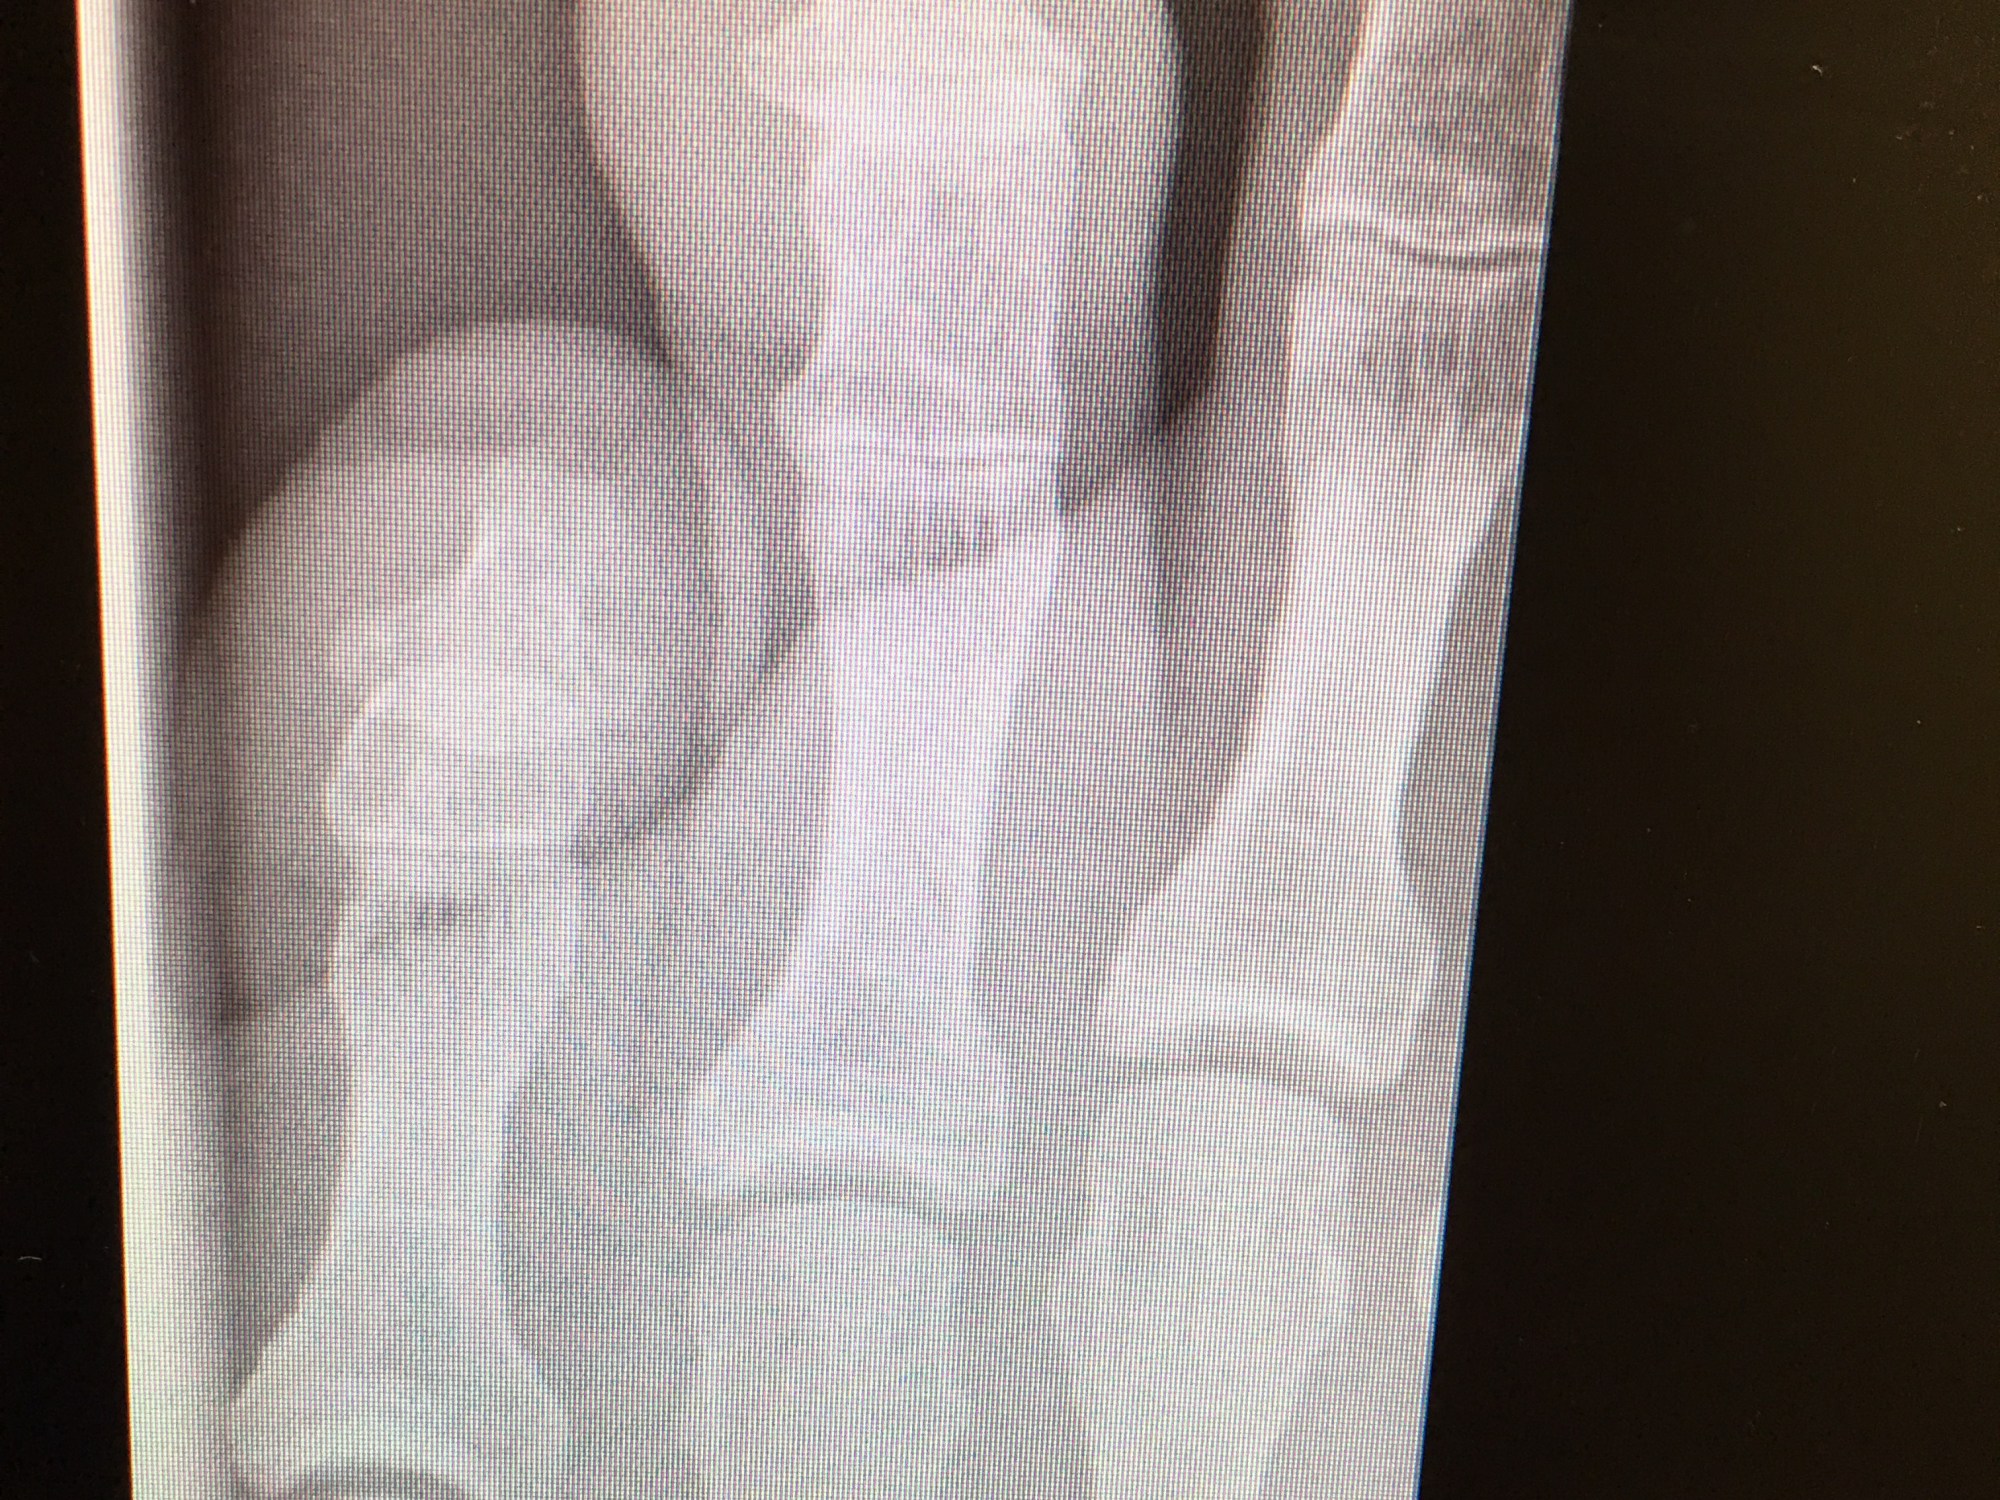

And here’s the view inside my foot.

It’s a fracture of my 4th toe, but luckily it’s “nondisplaced” – a hairline fracture.

All I need to do is “buddy splint” for the next 4-6 weeks. Third toe: will you be My Buddy?